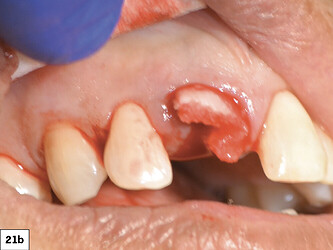

After the tooth was extracted, the site was thoroughly curetted. A pilot drill was used to begin the osteotomy, which was enlarged to the correct size for the implant. Prior to placing the implant, OsteoGen strip alloplast was re-hydrated with sterile saline and then placed in the socket against the wall adjacent to the gap. Hahn™ Tapered Implant (Glidewell Direct; Irvine, Calif.) was driven into place, and the graft material filled the gap. A healing abutment was placed and the site sutured with a Reli® REDISORB® PRO PGA 4-0 suture.